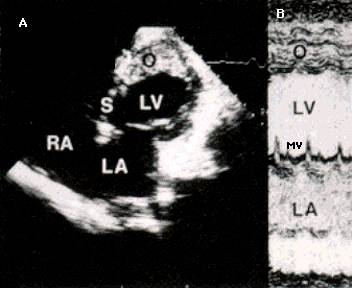

Ecocardiografia permite evaluarea afectarii functiei contractile, excluderea unor boli valvulare sau pericardice. Se apreciaza forma si functia VS (tipic VS globulos cu functie contractila global alterata), gradul insuficientelor valvulare, prezenta trombozei intracavitare (intraatriala sau intraventriculara). Cresterea dimensiunilor cavitatilor stangi si drepte este progresiva cu cresterea clasei functionale NYHA. Producerea emboliilor se asociaza cu dimensiunea VS si fractia de ejectie (FE).

Ecocardiografia

Confirma diagnosticul de CMH, cuantifica elementele morfologice - distributia hipertrofiei, functionale - hipercontractilitatea VS si hemodinamice - gradientul intraventricular.

Caracterele ecocardiografice sunt :